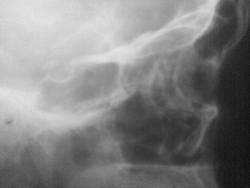

У меня на работе есть заготовленые схемы и слайд КТ. в понедельник выставлю.

Вот где то так все выглядит.